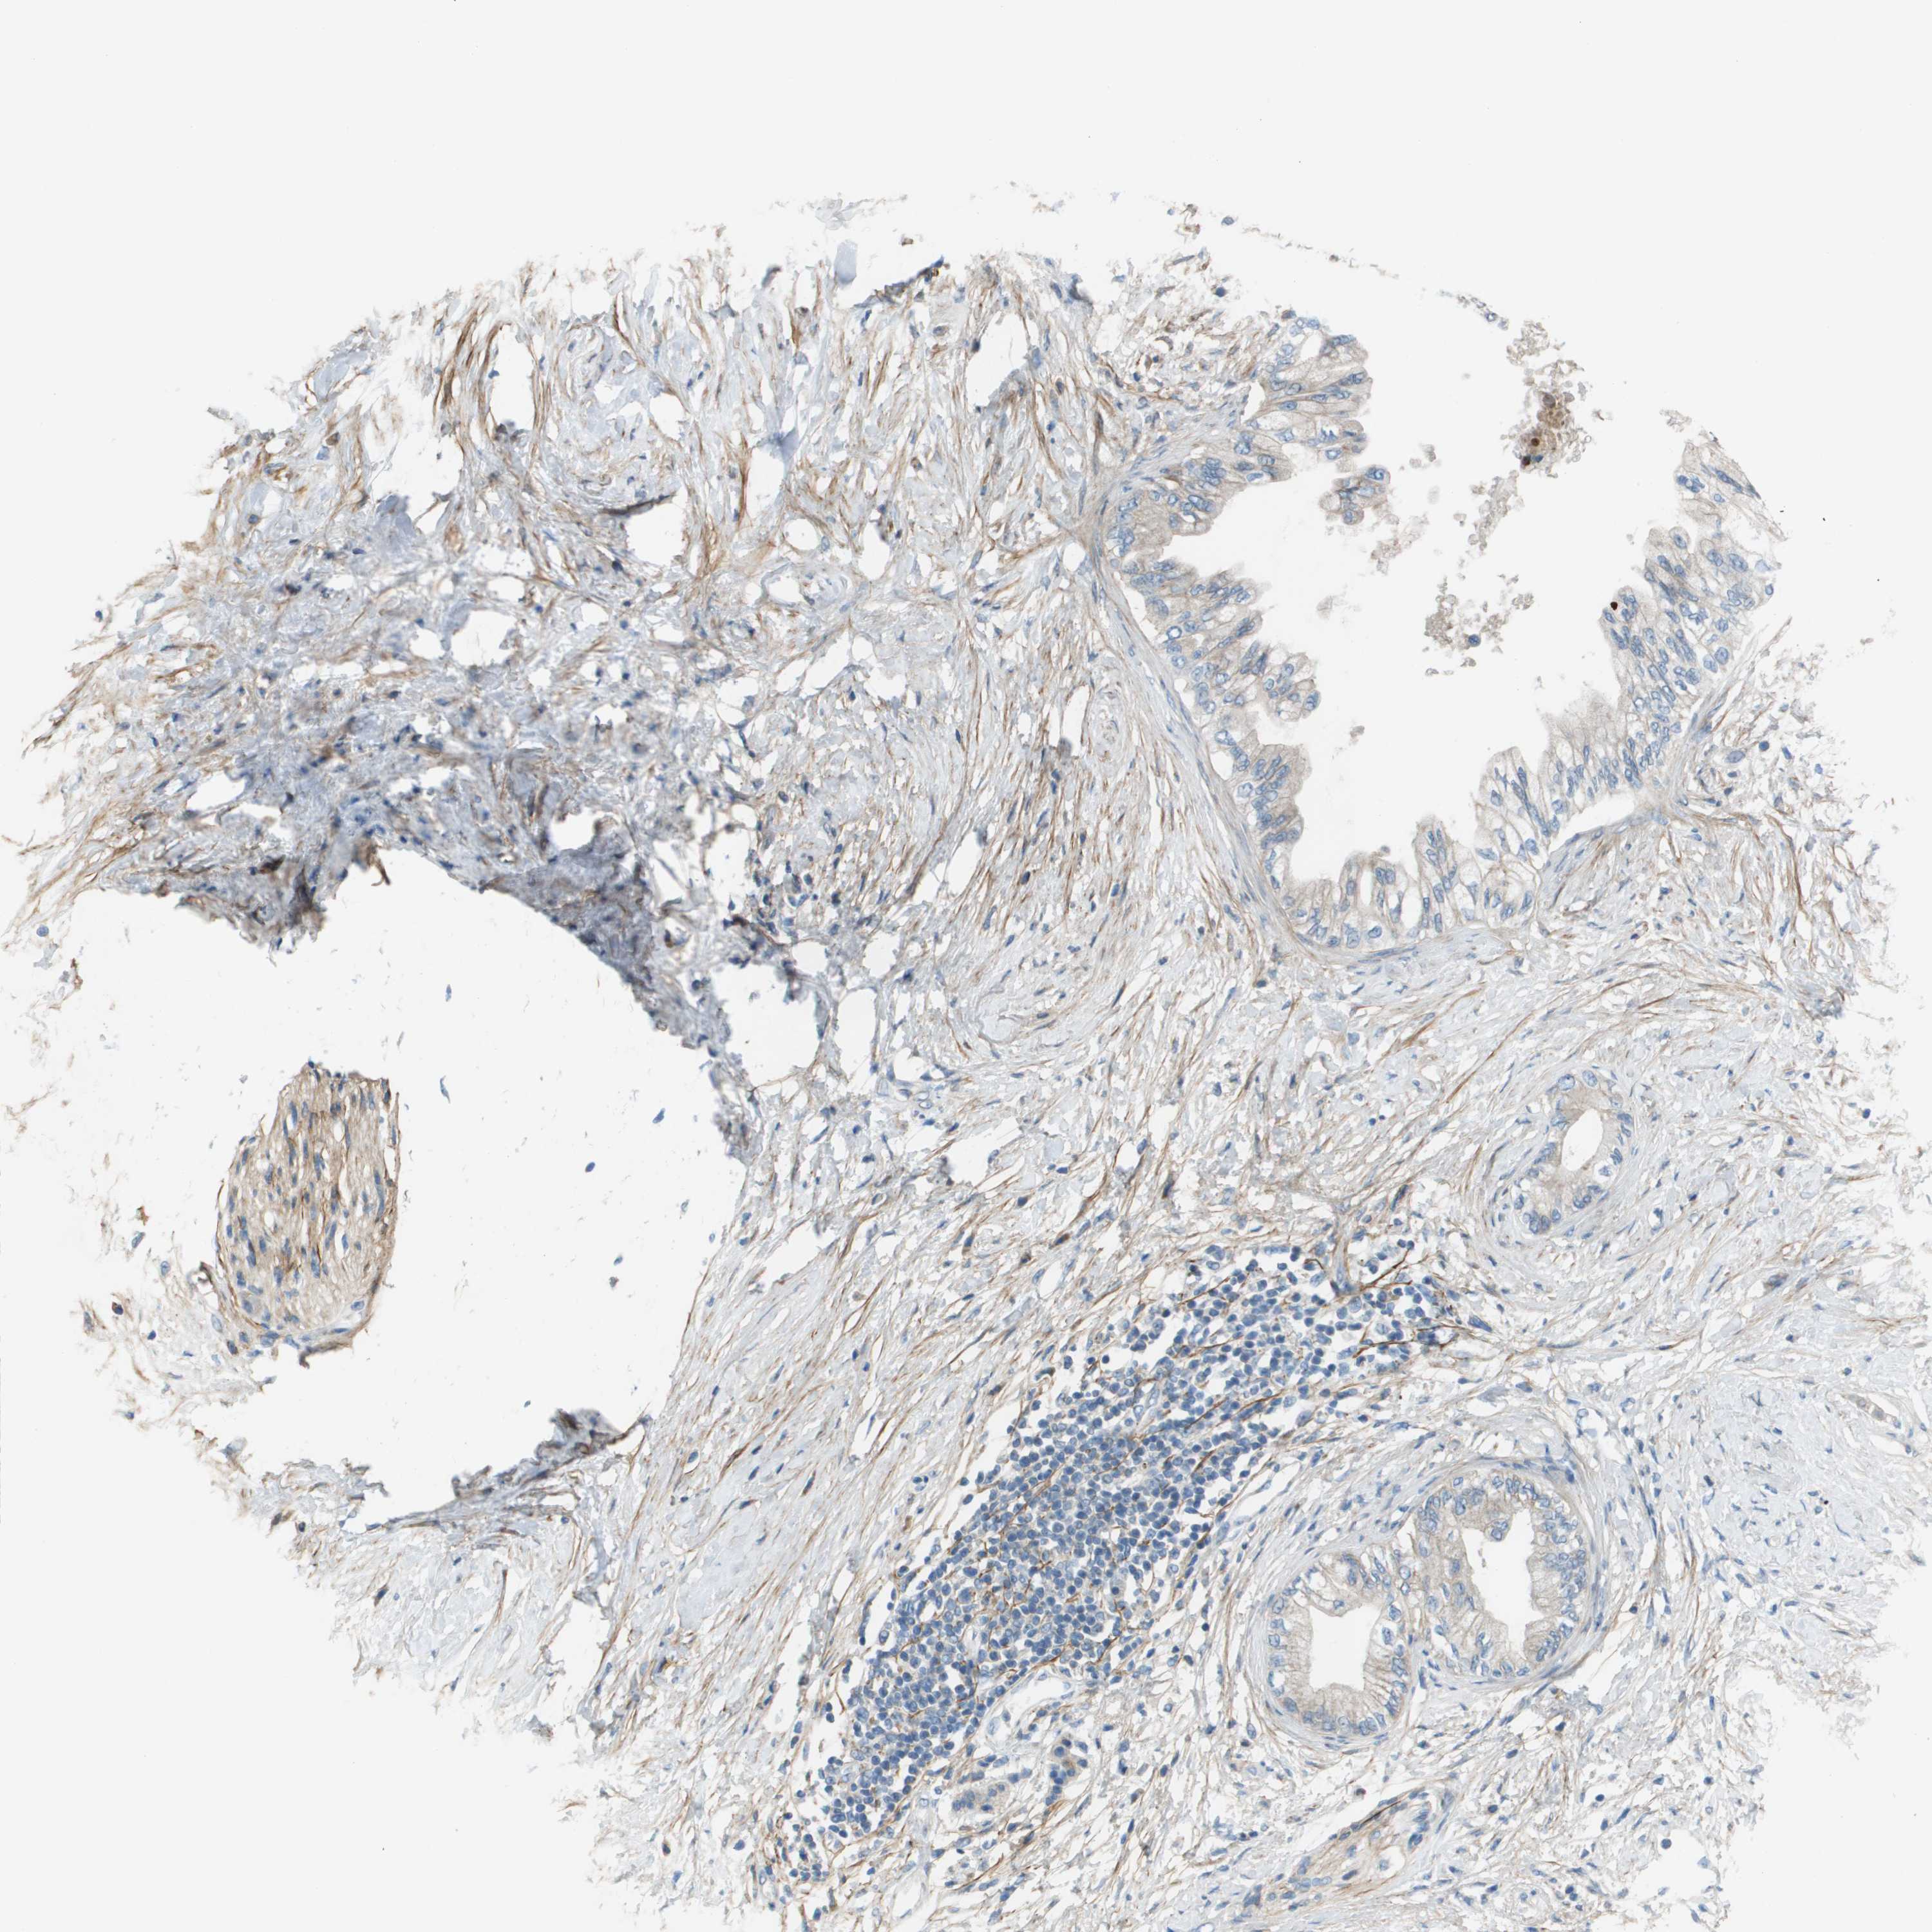

PANCREATIC CANCER - Protein expressioni

A mouse-over function shows sample information and annotation data. Click on an image to view it in a full screen mode. Samples can be filtered based on level of antibody staining by selecting one or several of the following categories: high, medium, low and not detected. The assay and annotation is described here.

Note that samples used for immunohistochemistry by the Human Protein Atlas do not correspond to samples in the TCGA dataset.

Antibody stainingi

Antibody staining in the annotated cell types in the current human tissue is reported as not detected, low, medium, or high, based on conventional immunohistochemistry profiling in selected tissues. This score is based on the combination of the staining intensity and fraction of stained cells.

Each image is clickable and will lead to virtual microscopy that enables deeper exploration of all samples and also displays staining intensity scores, fraction scores and subcellular localization as well as patient and tissue information for each sample.

Antibody HPA011762

Antibody HPA017086

Staining

High

Medium

Low

Not detected

Intensity

Strong

Moderate

Weak

Negative

Quantity

>75%

75%-25%

<25%

None

Location

Nuclear

Cytoplasmic/membranous

Cytoplasmic/membranous,nuclear

Adenocarcinoma, NOS

Adenocarcinoma, metastatic, NOS